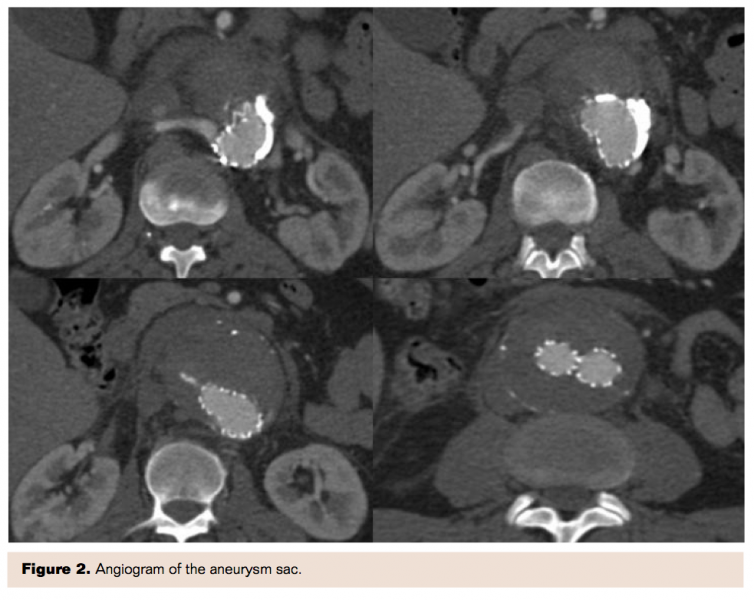

For selective catheterization of the aneurysm sac, over a 0.035˝ guidewire, a 5 Fr Simmons Imager II catheter (Boston Scientific) was introduced between the proximal stent-graft attachment site and the aortic wall. By using manual injection of contrast, the origin of the type IA endoleak was evaluated. A 2 Fr Excelsior 1018 microcatheter (Boston Scientific) was advanced coaxially through the 5 Fr catheter into the endoleak inflow and a selective angiogram of the aneurysm sac was performed (Figure 2). A mixture of 0.5 mL of Histoacryl NBCA resin (B. Braun) and 3.5 mL of Lipiodol oil-based iodine contrast (Guerbet) was prepared. The microcatheter was flushed with 5% dextrose solution to prevent premature precipitation of NBCA. Under continuous fluoroscopic guidance, a total of 3 mL of 12.5% NBCA solution was injected slowly through the microcatheter for 25 seconds; meanwhile the catheter was gradually withdrawn toward the leading edge of the graft to form a cast within the endoleak inflow (Figure 3). Both catheters were withdrawn from the patient within seconds before complete polymerization could occur.